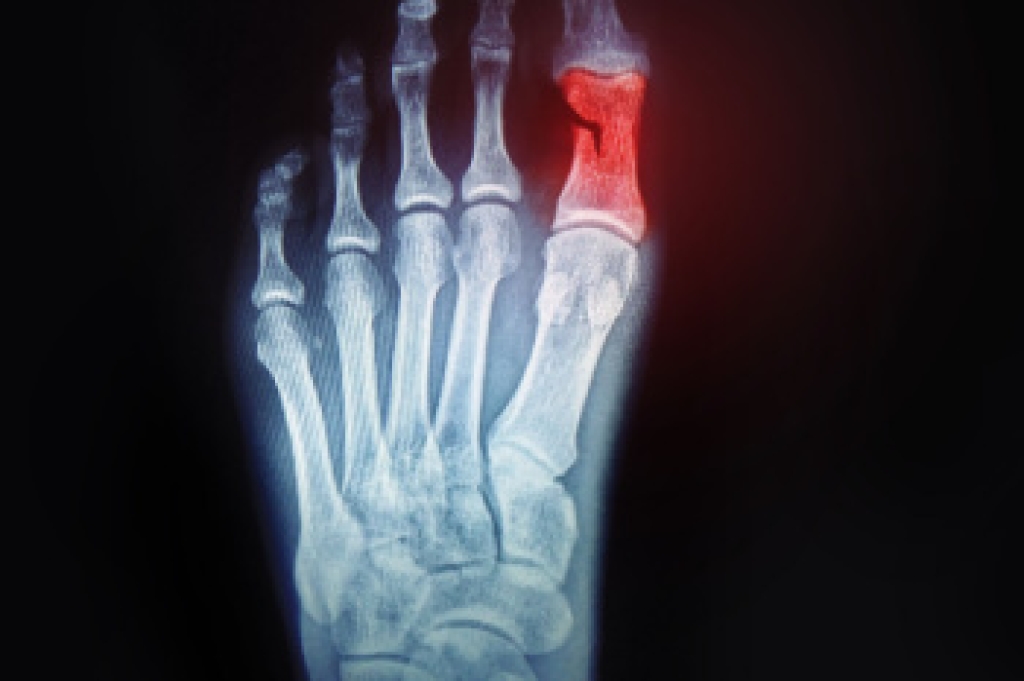

Falls among seniors are a significant concern, often resulting from a combination of factors. Common causes include muscle weakness, poor balance, vision problems, and environmental hazards like clutter or uneven floors. Medication side effects and medical conditions such as arthritis can also contribute to fall risk. To prevent falls, it is important to implement several practical strategies. Ensure the home environment is safe by removing trip hazards, installing grab bars, and improving lighting. Encourage regular exercise to enhance strength and balance like walking or specialized fall prevention classes. Regular eye exams and reviewing medications can also help address underlying issues. If you have injured your foot or ankle from falling, it is suggested that you consult a podiatrist who can treat various conditions.

Every 11 seconds, an elderly American is being treated in an emergency room for a fall related injury. Falls are the leading cause of head and hip injuries for those 65 and older. Due to decreases in strength, balance, senses, and lack of awareness, elderly persons are very susceptible to falling. Thankfully, there are a number of things older persons can do to prevent falls.